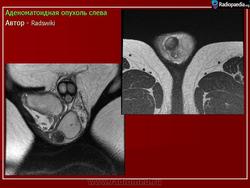

Доброкачественная гиперплация предстательной железы